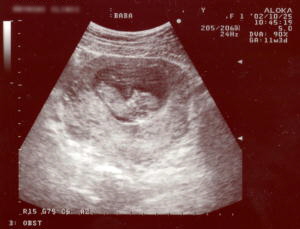

10/25は診察の日でした。

今5センチで順調に育っているとの事。

血液検査やお腹にゼリーを塗って超音波したり、心臓の音も聞いたようです。